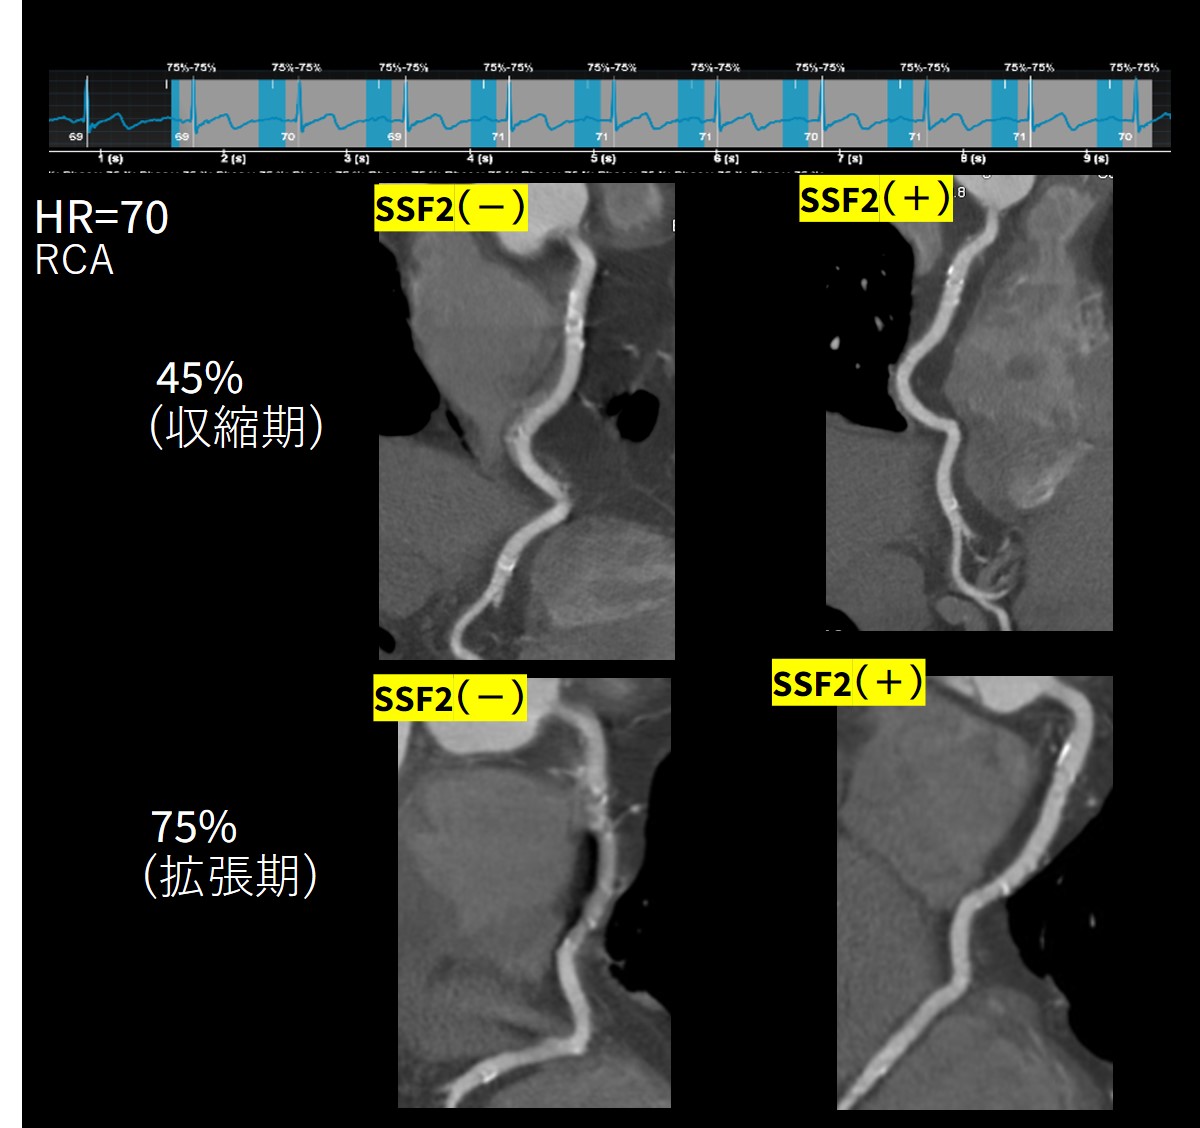

◆症例1)高心拍症例

心拍数70台 洞調律で撮影

RCAをPhase 45%(収縮期)で再構成

左はSSF2(-) 右は SSF2(+)

明らかにSSF2(+)の画像でMotion artifactがなく

鮮明に描出されていることがわかる(Fig.3)

しかし、SSF2が優秀なのはそれだけではない。

「冠動脈CTの経験が豊富な放射線技師であれば」心拍数70台の最適静止心位相は収縮期である事を知っている。しかし全ての技師が精通している訳ではない。下段に同じ症例の拡張期相( Phase 75%)のSSF2有無の比較画像を見て貰いたい。当然の如くSSF2処理を行う前においては全く静止位相は得られていない。しかしSSF2をかけた画像は全くMotion artifactを認めない。つまり「放射線技師の経験年数を問わず誰でも」冠動脈CT撮影が可能になった!

『長時間フェーズ探し』業務から解放された瞬間である。

Fig.3 高心拍症例での拡張期におけるSSF2におけるMotion抑制